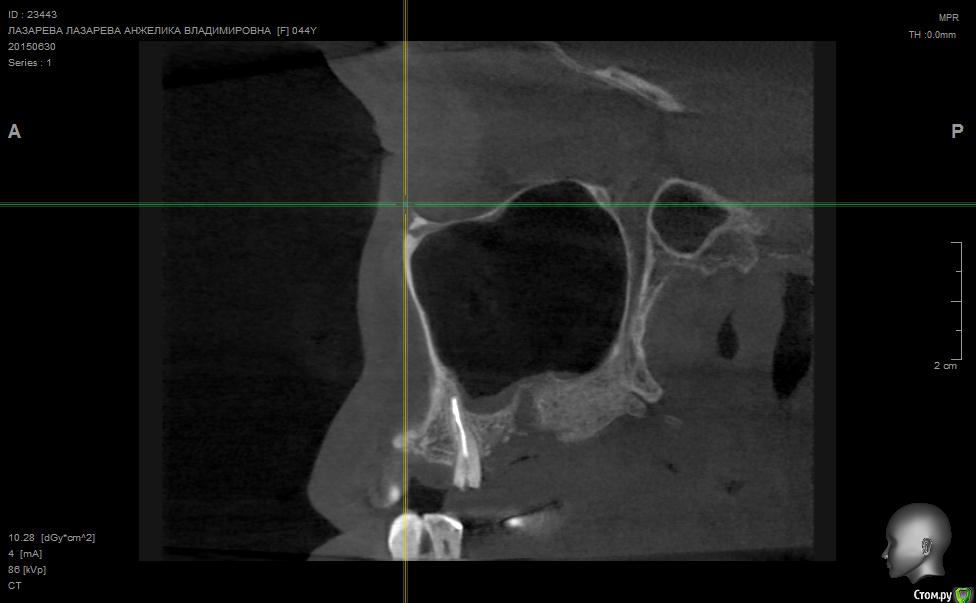

Angelika Опубликовано 2 июля, 2015 Поделиться Опубликовано 2 июля, 2015 Добрый день!Помогите,пожалуйста!!!!!!8 мая имплантолог(!) удалил 2 зуба-27(резерцин-формалиновый) и 28 (нелеченный).Удаление было очень долгим и травматичным,почуяв неладное,хотела убежать прямо из кресла.Последствия-одонтогенный гайморит,не считая незаживающих лунок .В начале июня отлежела в ЧЛХ(антибиотики,физио).26 июня сделала КТ.Нос пришел в норму более-менее,а вот челюсть....((((( Из заключения: 26,27,зубы отсутствуют. В альвеолярном отростке верхней челюсти в области отсутствующего 26 и 27 зуба визуализируется дефект костной ткани размерами до 9,6*14,0*7,2 мм с неровными и нечеткими контурами, с множественными мелкими и крупными секвестрами, с разрушеннымиоральной кортикальной пластинкой альвеолярного отростка верхней челюсти на протяжении до 12,9мм, и вестибулярной замыкательной пластинкой на протяжении до 19,1 мм. Рентгенологическихпризнаков свидетельствующих о наличии свищевого хода, ороантрального соустья - не выявлено,целостность нижней стенки левой верхнечелюстной пазухи полностью восстановлена на всем протяжении. Положительная динамика от 26.05.15г. В альвеолярном отростке, в области корней отсутствующего 28 зуба, определяются нечеткиеконтуры лунки удаленного зуба и единичный фрагмент корня размерами до 1,9*1,7*2,7 мм. В областиотсутствующего 28 зуба и бугра верхней челюсти слева визуализируются единичные мелкие участки остеопороза костной ткани альвеолярного отростка верхней челюсти, в следствие исхода воспалительного процесса. Посоветуйте,пожалуйста,нужно ли удалять обломок корня 28 зуба,если он такой маленький,а лунка уже затянулась.Что мне делать,как это залечить,болит вся челюсть с левой стороны.(((((( О имплантах и забыла уже,восстановиться бы после такой травмы.....Помогите!!! Что делать,как залечить все это?Снимки прилагаю. Ссылка на комментарий

Alejandro Опубликовано 2 июля, 2015 Поделиться Опубликовано 2 июля, 2015 На бумаге страшнее, чем на снимке. Лучший врач для Вас теперь - время. Со временем, кстати, станет понятно: что делать с остатком корня, экстренности пока никакой нет. Успокойтесь, сложные удаления довольно часто встречаются. Очень хорошо, что нет ороантрального сообщения. 2 Ссылка на комментарий

Bier Опубликовано 5 июля, 2015 Поделиться Опубликовано 5 июля, 2015 нет. У Вас на рентгене картина свежего удаления. Т.е. в рамках нормы 2 Ссылка на комментарий

Bier Опубликовано 7 июля, 2015 Поделиться Опубликовано 7 июля, 2015 думаю, что проблем там нет. На снимке все не так плохо, как в описании. Все хорошо будет. Ссылка на комментарий